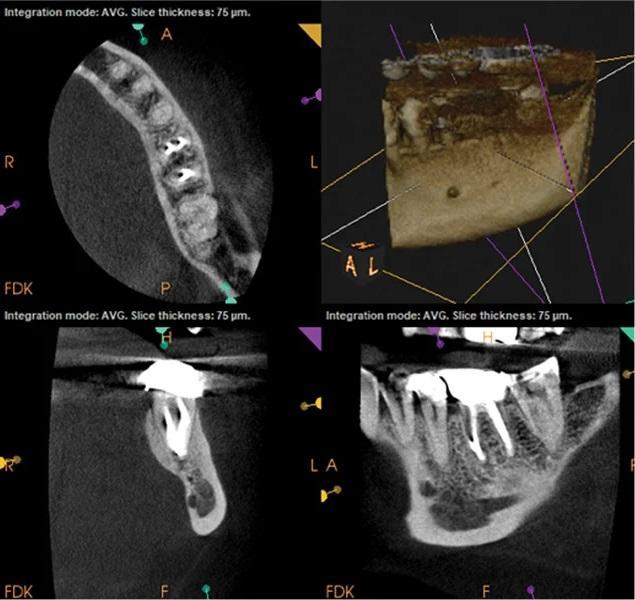

Наличие четко определяемых проблем или технических ошибок при первичном эндодонтическом лечении также играет важную роль в прогнозировании исходов повторного лечения. Исследования показывают, что результаты повторного лечения часто обратно пропорциональны качеству первичного лечения. Когда причины неудачи первичного лечения очевидны и поддаются коррекции (например, пропущенный канал или неполная обтурация), прогноз повторного лечения, как правило, более предсказуем, поскольку возможна целенаправленная коррекция выявленных дефектов (фото 2–5).

Фото 2–5. Клинический случай 2. Выявляемые причины неудачи первичного эндодонтического лечения, как правило, ассоциированы с более предсказуемым исходом повторного лечения.

Фото 2: Предоперационная периапикальная рентгенограмма, демонстрирующая ранее не выявленную анатомию в зубе 36.

Фото 3: Предоперационная КЛКТ. Отмечаются неполное пломбирование и периапикальная радиолюцентность, связанные с медиальным каналом.

Фото 4: Периапикальная рентгенограмма сразу после лечения.

Фото 5: КЛКТ через 3 месяца после лечения. Отмечается регресс периапикальной патологии в области медиального канала.